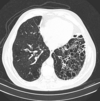

general bronchogenic carcinoma

“Lung cancer”

what is this the leading cause of? what are the two types? where are the four locations these mets are likely to spread? what is the main cause of these? what are 7 symptoms associated with lung cancer in general?

leading cause of cancer in men and women

made of two categories:

- small cell lung carcinoma

- non small cell lung carcinoma

mets to brain, bone, liver, lymph

SX:

****ASYMPTOMATIC, mostly incidental finding on CXR****

- ***change in nature of cough (squamous, small cell)

- hemoptosis

- vague nonpleuritic chest pain

- reccurent pneumonia

- WEIGHT LOSS ANOREXIA ASTHENIC (CLASSIC)

- HYPERCALCEMIA, don’t miss this

cigarette smoking is the main cause, 85% of lung cancer in smokers